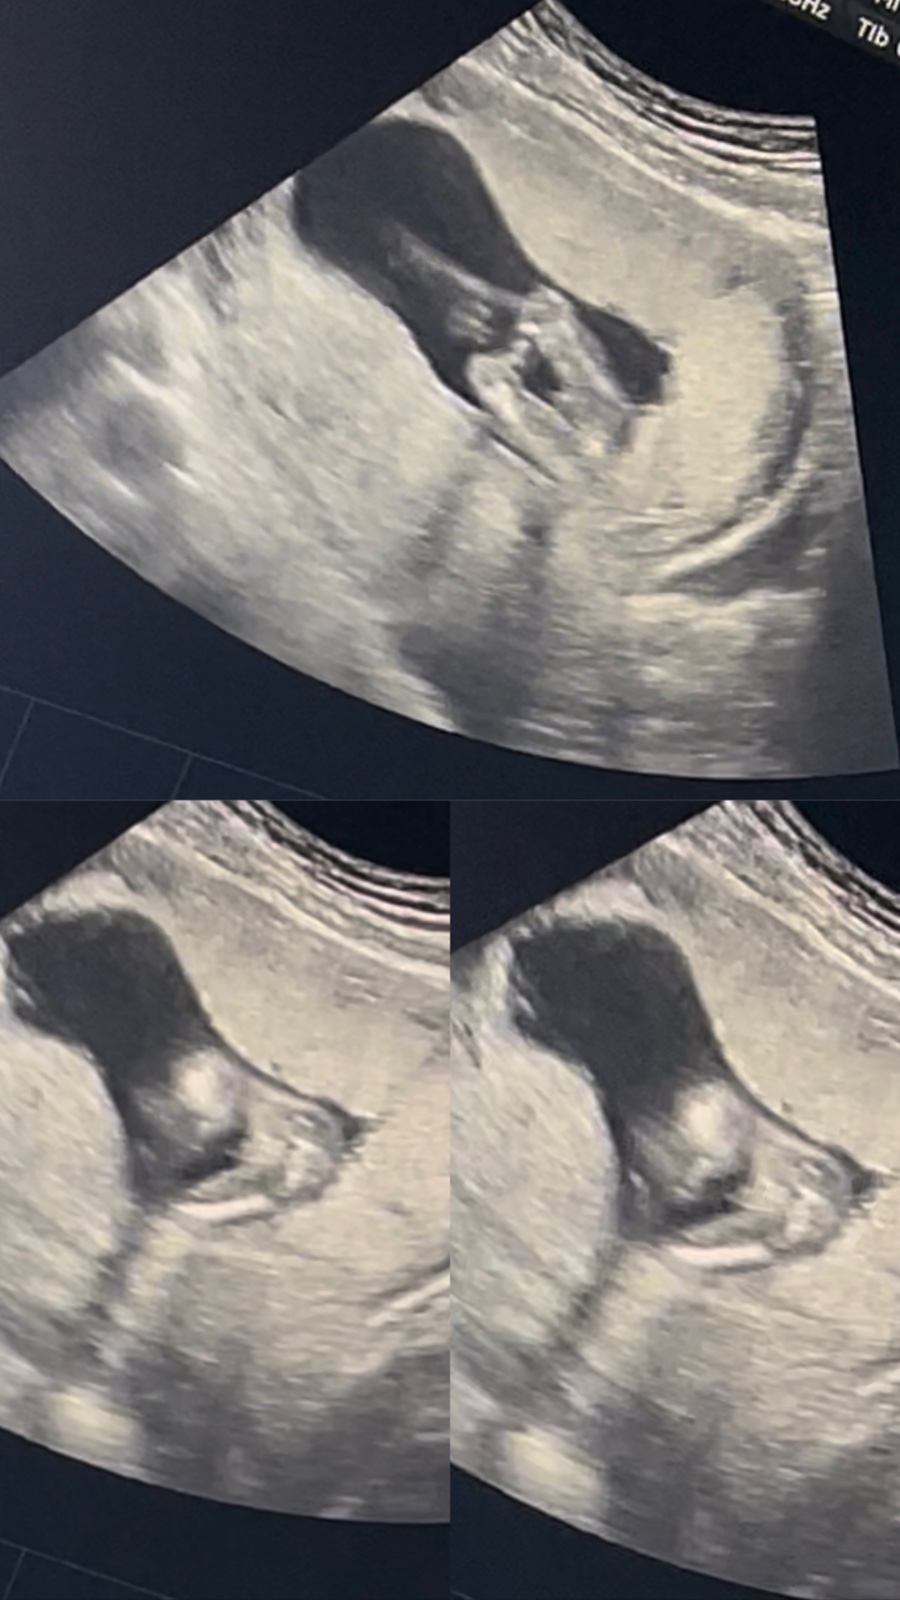

Jak poznat pohlaví dítěte podle ultrazvuku?

Jak se zjišťuje pohlaví dítěte?.